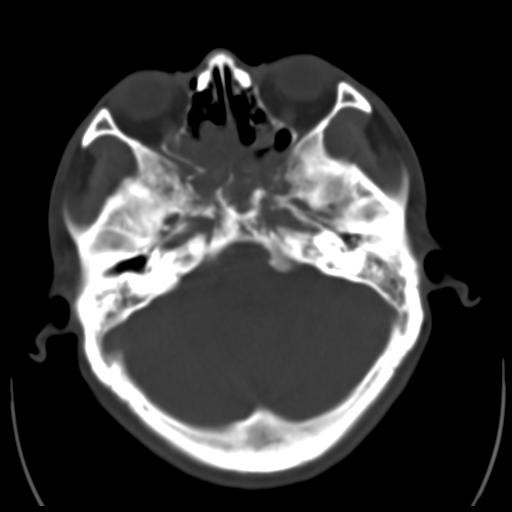

35m 鼻子时不时流血,头及右侧面部痛,颈部淋巴结未见明显大

骨窗

蝶窦,后组筛窦及鼻咽部团块状软组织影,骨壁破坏,病变较广泛。考虑恶性肉芽肿。建议活检。

颅底骨质明显破坏 支持鼻咽癌 但病灶的边缘毛糙 不能除外炎性

考虑中线肉芽肿(鼻硬结病),次之tb或真菌感染性肉芽肿,病变形态不像肿瘤,建议增强及活检。

蝶窦,后组筛窦及鼻咽部团块状软组织影,骨壁破坏,病变较广泛。考虑炎性肉芽肿性病变可能。建议活检。